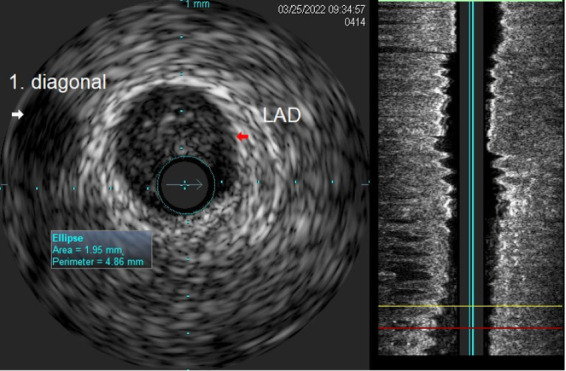

Planning and guiding PCI in a complex intervention is very important and one of the most important decisions is the one on whether to use one or two stent bifurcation techniques. Unfortunately, this can easily turn into complication and the need to alter the procedural strategy. The main points to be considered when deciding on the PCI strategy are related to both procedural safety and long-term outcomes. Provisional stenting has been recommended as the default technique for most coronary bifurcation lesions. In this paper, we describe the case of a patient scheduled for elective procedure of bifurcation lesion of LAD/D1. Our planned strategy was provisional stenting of LAD, using one stent for LAD, DCB for D1. Due to the complication that occurred, i.e., dissection of LAD after LAD stenting, we changed the strategy to two-stents technique strategy, using Culotte technique.

在复杂的介入治疗中规划和指导PCI是非常重要的,其中最重要的决定之一是是否使用一种或两种支架分叉技术。不幸的是,这很容易变得复杂,需要改变程序策略。在决定PCI策略时要考虑的要点与手术安全性和长期结果有关。临时支架置入术被推荐为大多数冠状动脉分叉病变的默认技术。在本文中,我们描述的情况下,病人计划择期手术的分叉病变的LAD/D1。我们计划的策略是LAD临时支架置入,LAD使用一个支架,D1使用DCB。由于LAD支架置入术后LAD发生夹层等并发症,我们将策略改为双支架技术策略,采用Culotte技术。